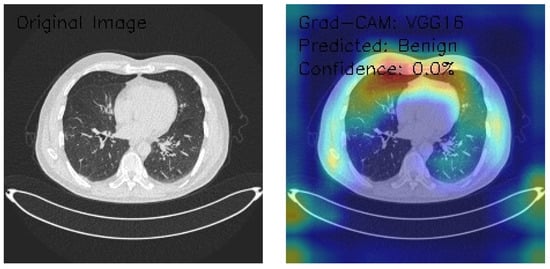

VGG16 Model Analysis of Lung CT Images with Grad-CAM Visualization

The results section of this analysis provides a detailed examination of three axial chest CT images analyzed through the VGG16 architecture, a widely recognized convolutional neural network model. We employed Grad-CAM, an advanced visualization technique, to gain insights into the model’s decision-making processes and focus areas. This method highlights the regions of the input images the model considers most significant when making predictions, offering a comprehensive view of its attention patterns. By integrating Grad-CAM with the VGG16 framework, this analysis illustrates the model’s effectiveness in interpreting medical imaging data and provides a transparent mechanism to evaluate its decision rationale. The findings presented aim to shed light on the nuanced interactions between the neural network and the image features, contributing to the broader understanding of AI-assisted diagnostic methodologies.

Figure 15 shows the analyzed CT image presenting scattered nodular opacities, with Grad-CAM visualizations emphasizing bilateral upper lung fields and an intense, asymmetric activation pattern, predominantly on the right side. The model classifies the image as Normal with a confidence score of 0.0% despite notable focal areas of high activation marked by yellow-red coloration. This discrepancy between the detected features and classification outcome highlights potential limitations in the model’s ability to translate activation insights into reliable predictions. The findings underscore the need for recalibration and refinement of classification and confidence scoring mechanisms to improve diagnostic accuracy and clinical reliability.

Figure 15.

Grad-CAM visualization (VGG16) highlighting nodular opacities in bilateral upper lungs with asymmetric right-side activation. (Source: author’s analysis from data, 2024).

Figure 16 shows the CT image demonstrating interstitial patterns with branching structures, and the Grad-CAM visualizations indicate bilateral peripheral activation, with strong emphasis along the lateral chest wall interfaces. The model classifies the image as Benign with a confidence score of 0.0%, reflecting significant uncertainty in its decision-making process despite the clear focus on relevant anatomical regions. The bilateral peripheral activation pattern suggests that the model effectively identifies features of interest, but the low confidence highlights a disconnect in translating these observations into reliable classifications. Enhancing the model’s calibration and optimizing its classification layers are crucial to improving its clinical utility.

Figure 16.

Grad-CAM Visualization of Interstitial Patterns in CT Using VGG16. (Source: author’s analysis from data, 2024).

Figure 17 shows the CT image depicting clear lung fields, with Grad-CAM visualization showing focal activation in the right upper lung and notable attention to the hilar regions. The activation pattern demonstrates a right-sided predominance, suggesting the model’s sensitivity to specific anatomical features. Despite these observations, the model classifies the image as Benign with a confidence score of 0.0%, indicating significant uncertainty. This mismatch between detected features and classification confidence suggests the need for model recalibration, improved classification layer optimization, and enhanced confidence scoring mechanisms to ensure reliable and actionable diagnostic outcomes.

Figure 17.

Grad-CAM Visualization of VGG16 for CT Image with Right-Sided Activation. (Source: author’s analysis from data, 2024).

The VGG16 model, applied to three chest CT images with Grad-CAM visualizations, demonstrates strong capabilities in localizing anatomical features but struggles with reliable classification due to uniformly low confidence scores. Image A, showing scattered nodular opacities, reveals intense bilateral upper lung activation with a predominant right-sided focus, yet is classified as Normal with 0.0% confidence. Image B highlights peripheral lung field activation and lateral chest wall emphasis in the presence of interstitial patterns, classified as Benign with 0.0% confidence. Image C, featuring clear lung fields, displays focal activation in the right upper lung and hilar regions, but is similarly classified as Benign with 0.0% confidence. While the model excels in highlighting regions of interest with precise and consistent attention patterns, its limited confidence and conservative classification behavior highlight the need for calibration and optimization. These findings suggest potential utility in feature detection and initial screenings, provided enhancements to confidence scoring and classification thresholds are implemented.